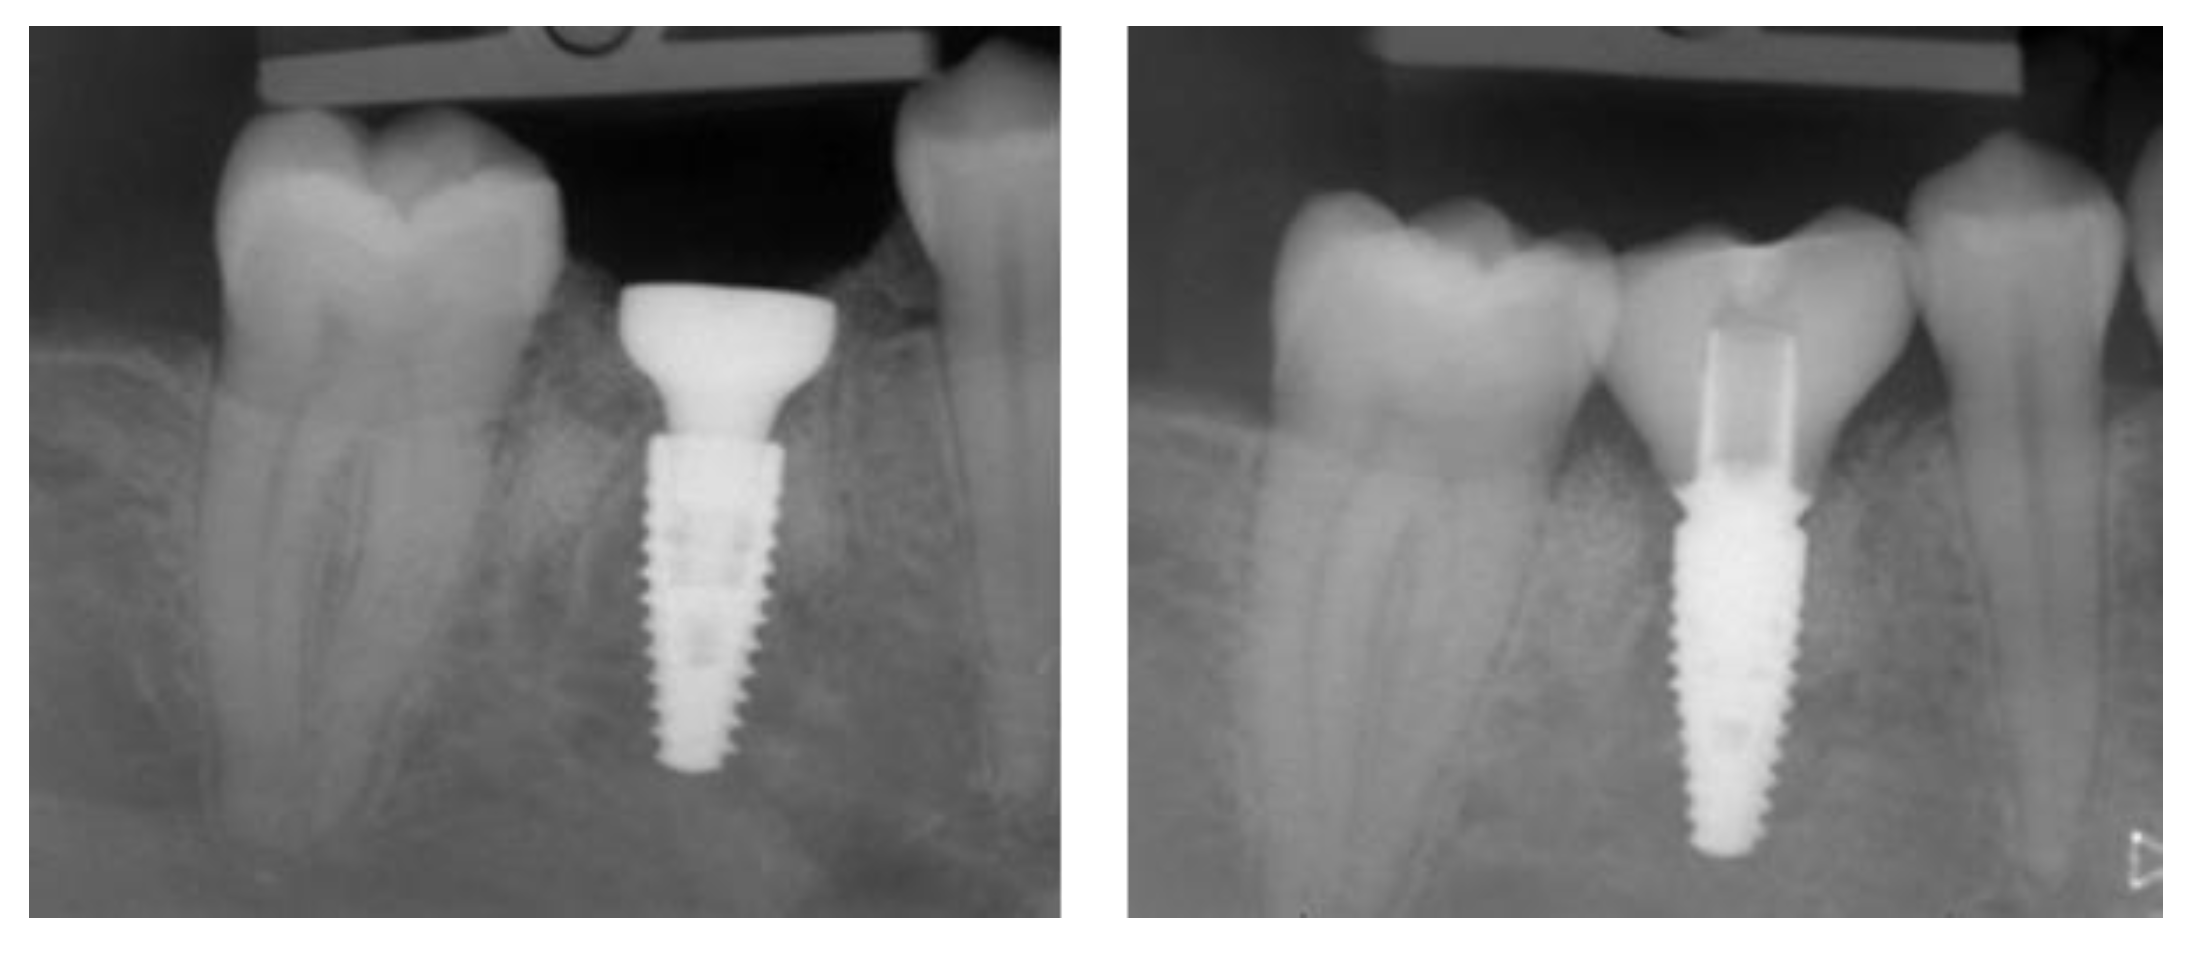

2.5. Individual Cases Description

- Case 1:

- Case 2:

- Case 3:

- Case 4:

- Case 5:

3.1. Clinical Results

3.2. Marginal Bone Level Outcomes

| Mesial Marginal Bone Level (2D) [mm] after Immediate Placement | ||||||||

| Marginal Bone Level (2D) [mm] after Delayed Placement | ||||||||